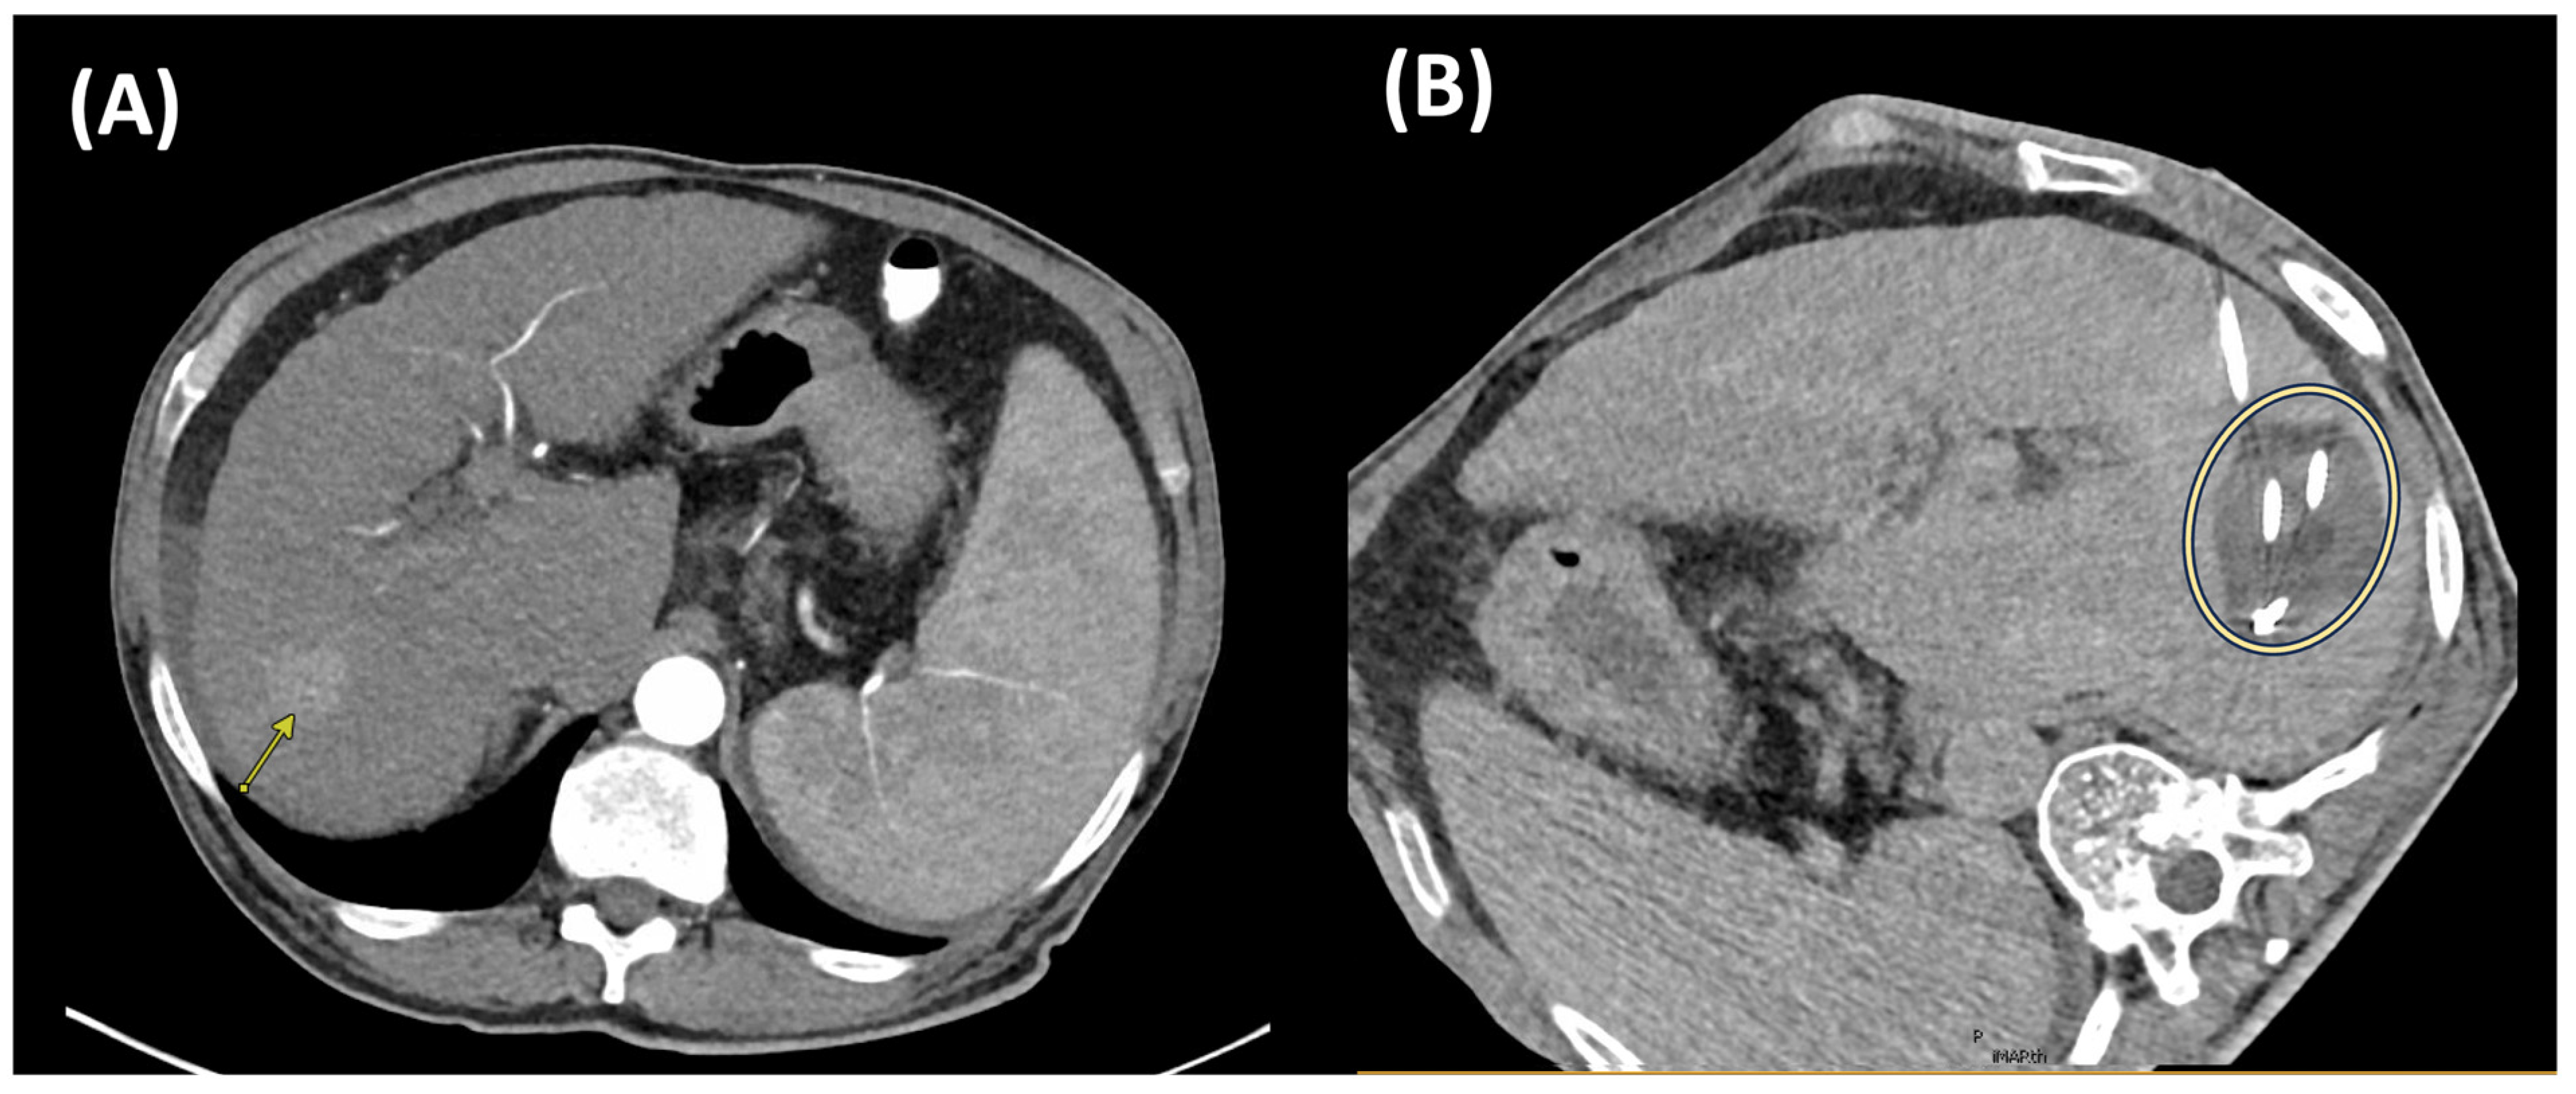

3.1. Irreversible Electroporation (IRE)